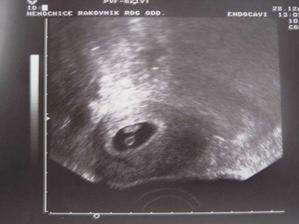

SRPŇÁTKA 2007 - fotky UTZ

album věnované mimískům, které se narodí v srpnu 2007 a jejich maminkám ze "Společného termínu SRPEN"